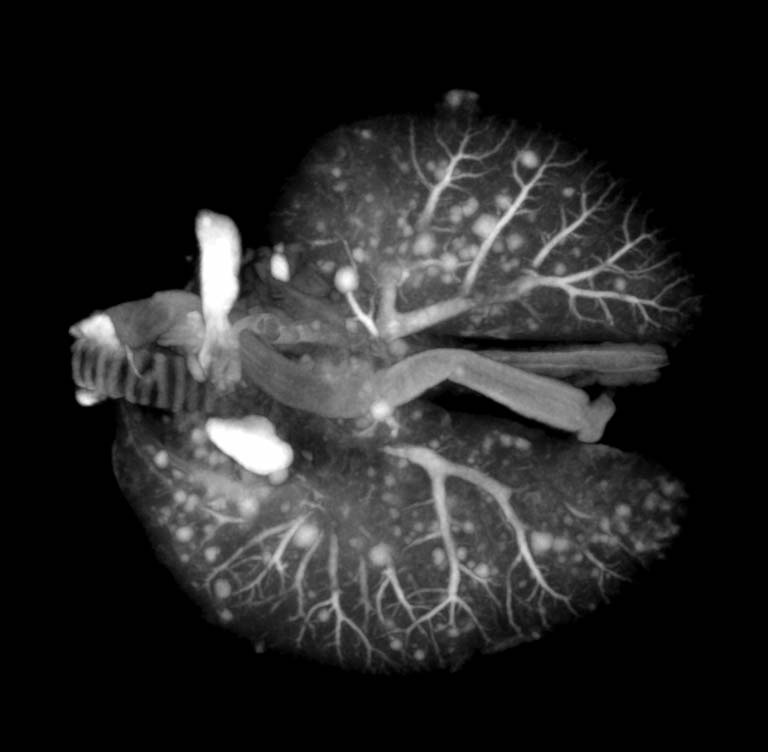

Viewing Lung Tumors in 3D, Image 3

Submitted by Milton Cornwall-Brady of the Applied Therapeutics and Whole Animal Imaging Core at the Koch Institute

"Mouse lungs were scanned in a microCT, generating a 3D dataset that allows researchers to count the number of tumors and measure their size. These images help us to understand the distribution of tumors within the lungs as well as quantifying any changes in the number/size of tumors due to whatever form of intervention (e.g., chemotherapy) is being tested. Although this can be done with traditional histology, with this method we obtain a full 3D measurement of all tumors present, not just a 2D slice through a random subset of tumors as one would get from histology."